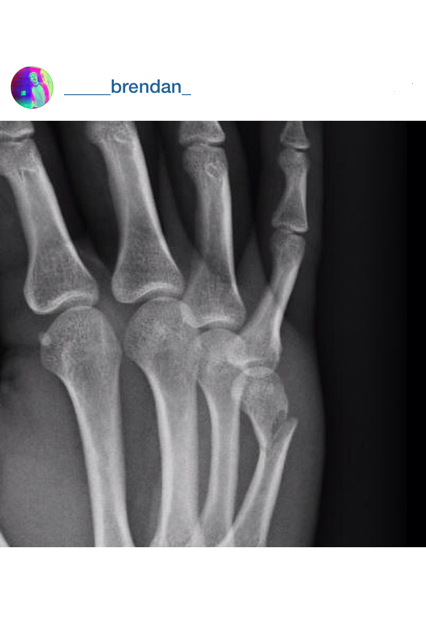

hand is down…

When this happens, it sucks.

Atleast a cast will look cool for 4 weeks…